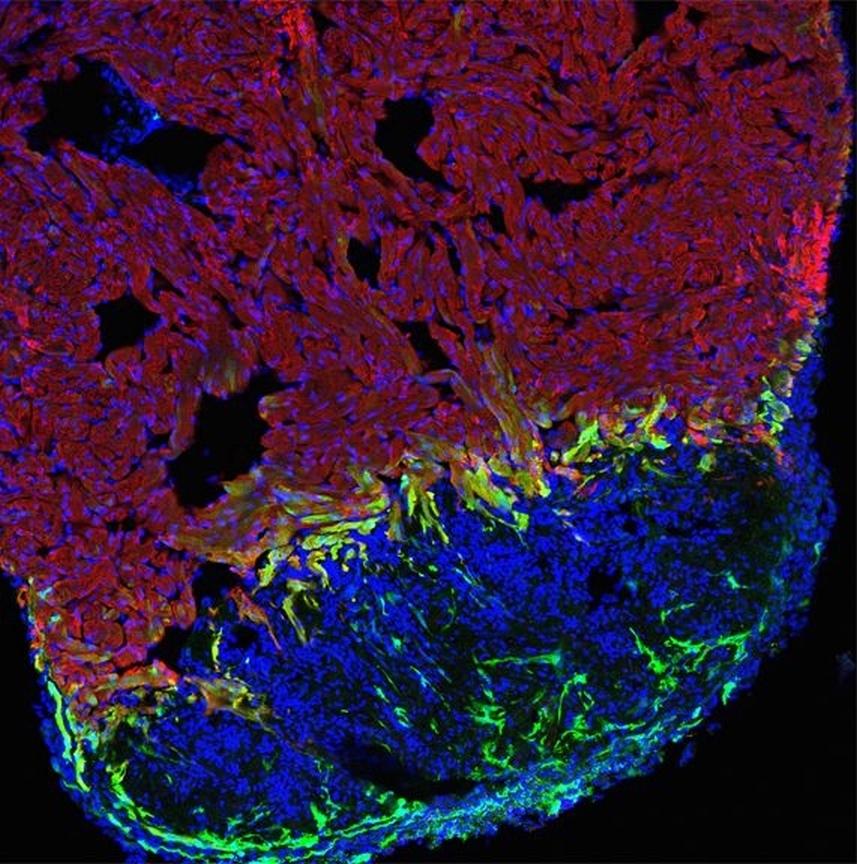

* gesundes Muskelgewebe rot, Wunde blau und aktivierte Herzmuskelzellen grün angefärbt